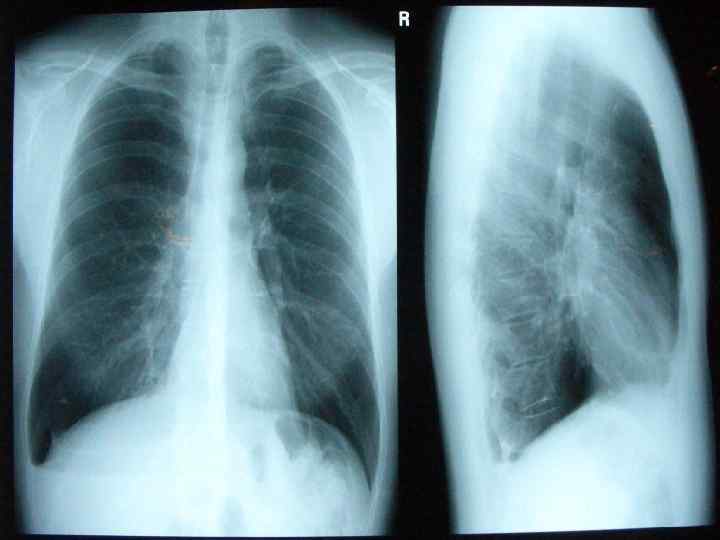

Общие сведения • Астма - это удушье разнообразной природы. При астме приступы удушья возникают внезапно, характеризуются выраженным затруднением и удлинением фазы выдоха. Приступы удушья и кашля появляются на фоне здорового состояния. Характерны для астмы повышенное содержание эозинофилов в крови, благоприятное действие адреналина. Астма - классическое инфекционноаллергическое заболевание, т. е. аллергия возникает на инфекцию, которая находится в верхних и нижних дыхательных путях. Оба пола с одинаковой частотой болеют бронхиальной астмой. Диагностику и лечение астмы необходимо проводить под контролем лор-врача в специализированных клиниках.

• Приступы астмы тяжелого течения характеризуются частыми длительными обострениями с наличием осложнений, опасных для жизни, частыми ночными симптомами, снижением физической активности, наличием сохраняющихся симптомов в межприступный период. • Фазы течения бронхиальной астмы: • обострение; • ремиссия. • Осложнения бронхиальной астмы: • легочные - эмфизема легких, легочная недостаточность, ателектаз, пневмоторакс; • внелегочные - дистрофия миокарда, легочное сердце, сердечная недостаточность.